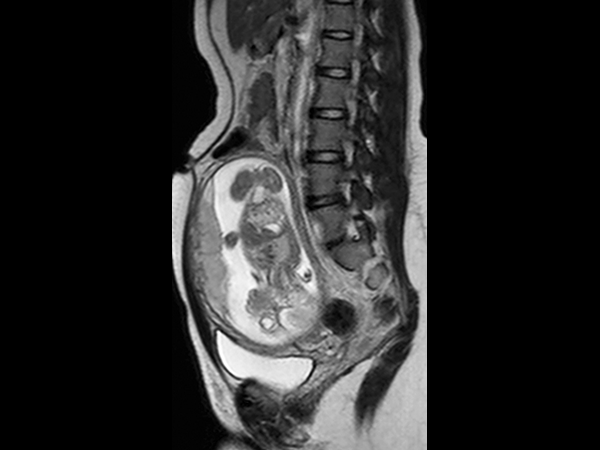

A 25-year-old female, 20 weeks pregnant, presented with right lower quadrant pain. Her white blood cell count was elevated, measuring 14.6. Ultrasound failed to visualize the appendix. Consequently, the patient was referred for MRI. The scan was performed on a 1.5T SmartPath to dStream system using the integrated Posterior coil and the Anterior coil. The exam includes 3-plane T2-weighted scans, 3-plane B-FFE scans and axial T2W SPAIR, all in breath holds < 15 seconds. The MR images demonstrate a distended appendix with adjacent fat stranding. The diagnosis is acute non-perforated retrocecal appendicitis, surgically confirmed. MRI successfully diagnoses appendicitis in pregnancy without using ionizing radiation or contrast. This 18-minute exam without contrast or ionizing radiation has replaced CT in pregnant women at our institution. We have performed over 60 cases in the last 5 years, with 9 positive, surgically confirmed. We saw no false positives, and to the best of our knowledge, no false negatives either. We usually start with ultrasound, but it is frequently negative in these patients. T2-weighted sequences are the mainstay for our diagnosis. With our SmartPath to dStream system, SENSE and dStream allow us to acquire these faster with improved signal. In these patients, who are often short of breath, the scan can be completed in 15 minutes or less.

Sagittal T2w TSE